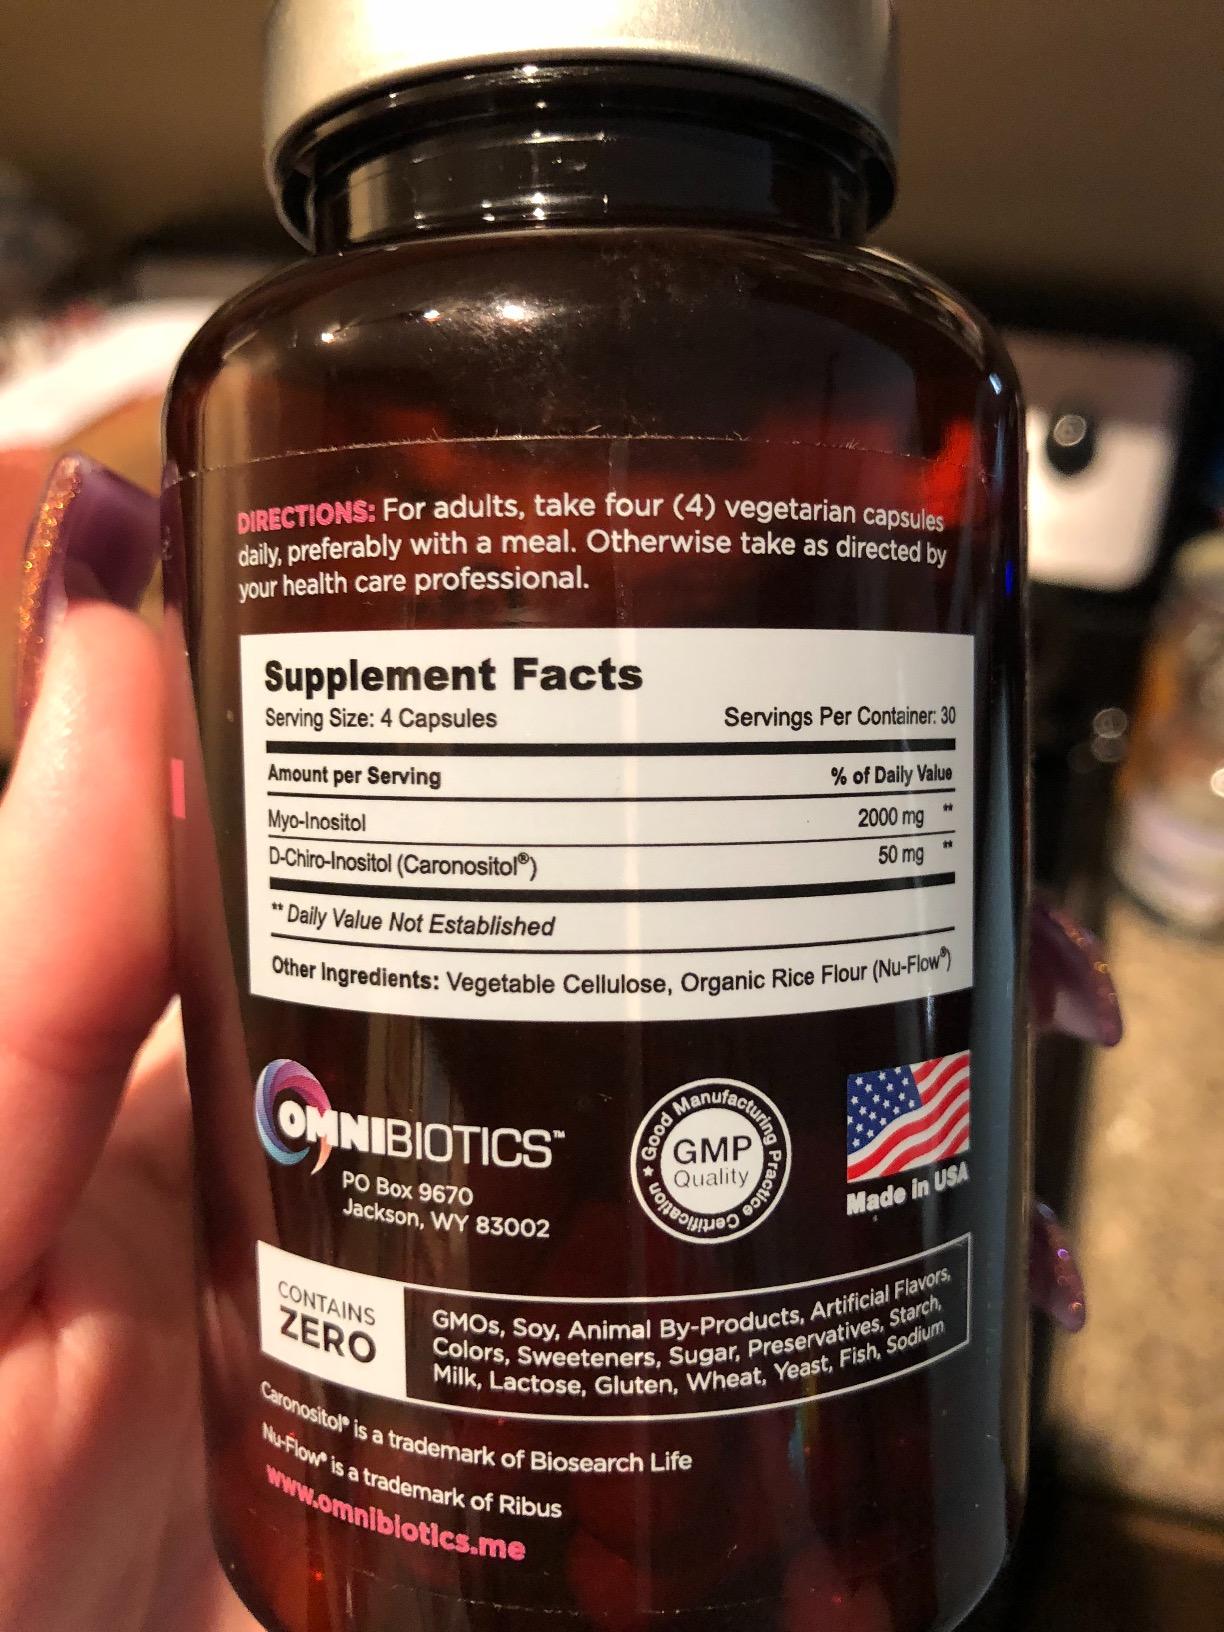

Myo-Inositol Plus & D-Chiro-Inositol | PCOS Supplement | Helps Promote Hormone Balance and Support Ovarian Function | Natural Fertility Supplements (120 Capsules)

OmniBiotics Myo-Inositol Plus with Caronositol features myo-inositol and

d-chiro-inositol at 2,000 mg and 50 mg each respectively, per serving. Myo-

Inositol Plus is a safe and effective myo inositol with d chiro supplement

option. 120 veggie caps 30 day supply These statements have not been

evaluated by the FDA. This product is not intended to diagnose, treat, cure,

or prevent any disease. Caronositol is natural D-chiro-inositol botanical

extract (minimum 95%) purified from carob pod by a solvent-free patented

process. ‣ Made In the USA within a FDA inspected, NSF and cGMP certified

facility ‣ 100% vegetarian / vegan friendly, Non-GMO ‣ Contains no gluten,

wheat, dairy soy, yeast, animal products, artificial colors, or artificial

preservatives

- 100% NATURAL, NON-GMO, NO BINDERS or ADDITIVES Our clinical-strength, Myo-Inositol Plus supplement is 100% free of: gluten, soy, nuts, dairy, sugar, animal by-products, artificial ingredients, chemicals, preservatives and fillers. We also do testing at every stage of the manufacturing process to ensure all ingredients are free of heavy metals. Made in the USA in a NSF-certified, FDA-registered, cGMP facility.

- Brand: OmniBiotics

- Flavor: Unflavored

- Primary Supplement Type: Myo-Inositol

- Unit Count: 120.00 Count

- Item Form: Capsule